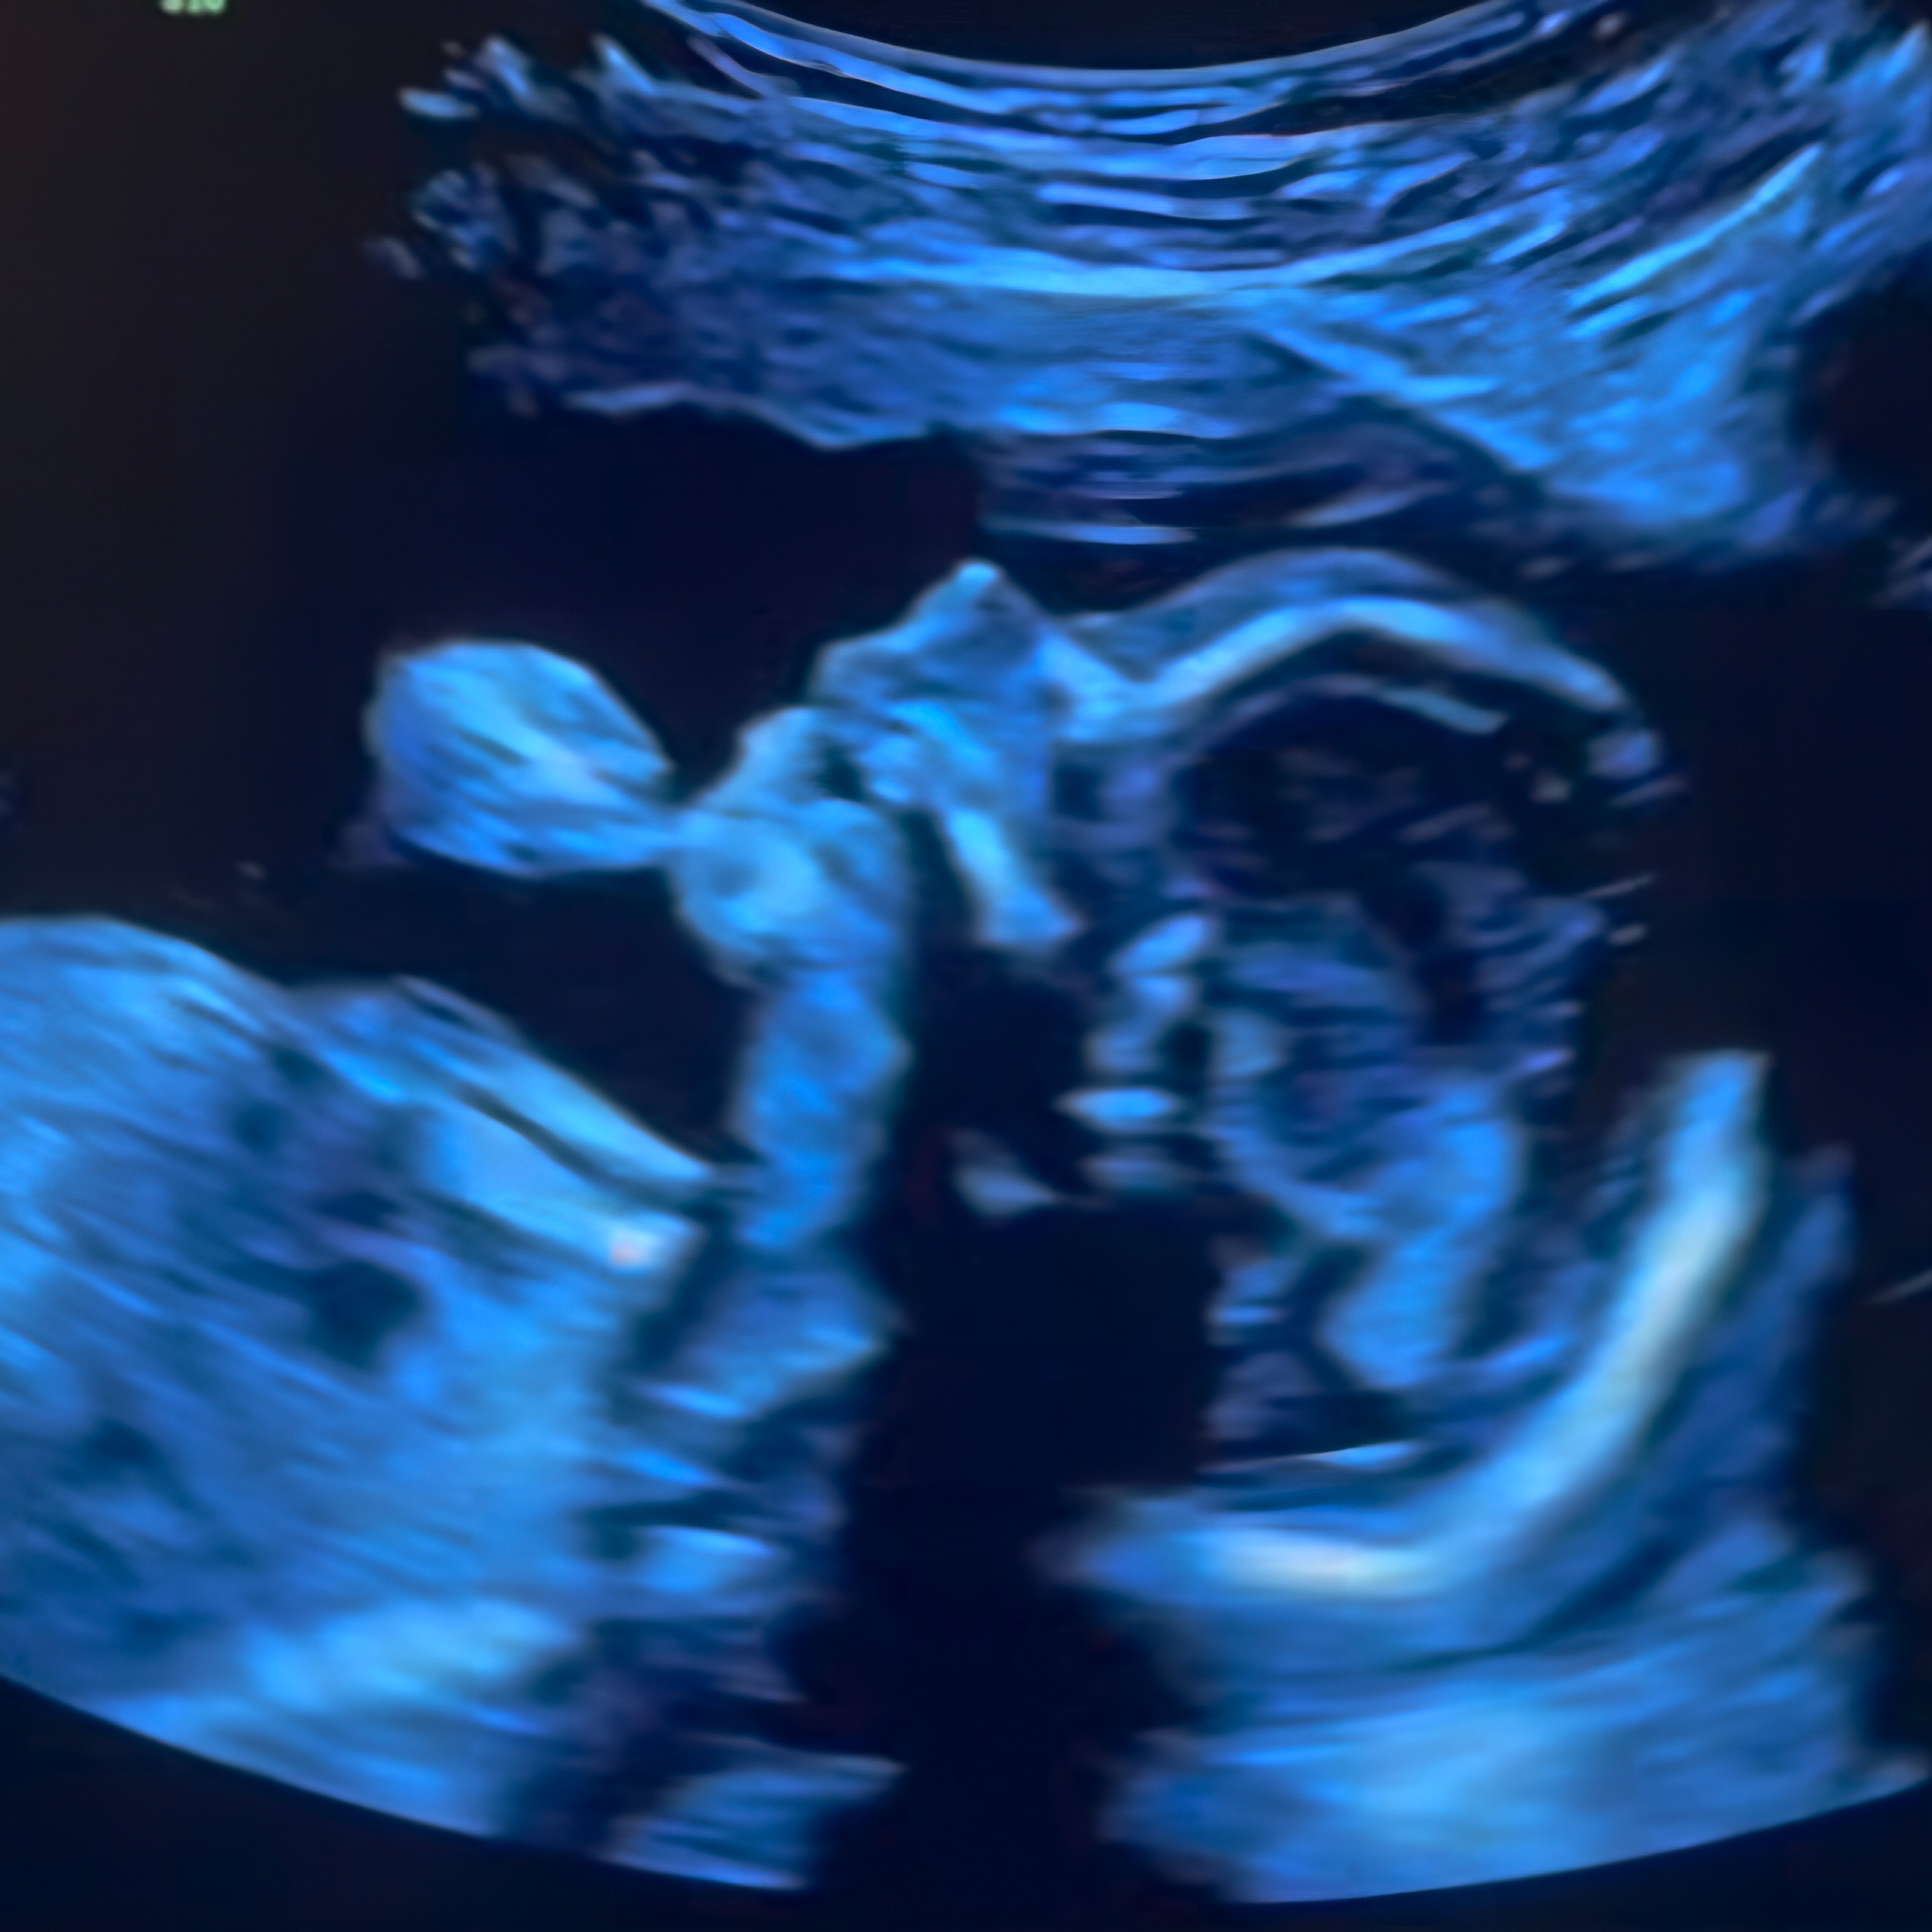

Imagine being told your baby’s first moments in the world will be a fight for survival. This is the reality facing Mike and Becca, whose unborn daughter has been diagnosed with several rare and complex conditions.

Her heart didn’t develop as it should. The chambers of her heart didn’t seal properly, allowing oxygenated and non-oxygenated blood to mix, and her arteries are twisted and misaligned, making it impossible for her heart to function as it should. One critical artery, which should supply blood to her lungs, is underdeveloped—so small that it won’t work.

As if this weren’t enough, there’s a pinch in the umbilical cord, slowing her development. This brings added risks, including the potential for intellectual disabilities. Right now, the family faces a lot of unknowns.

Doctors are preparing for her birth, but she’ll need immediate care to stabilize her fragile condition. She’ll spend 4-6 weeks in the hospital after birth, followed by her first major heart surgery at just 6-9 months old. And this will only be the beginning, as she’ll require additional surgeries as she grows.

To further complicate matters, the baby will likely need to be delivered early, around 37 weeks, to reduce the risk of stillbirth. This leaves the family juggling the needs of their older children and trying to prepare for the uncertainty ahead.